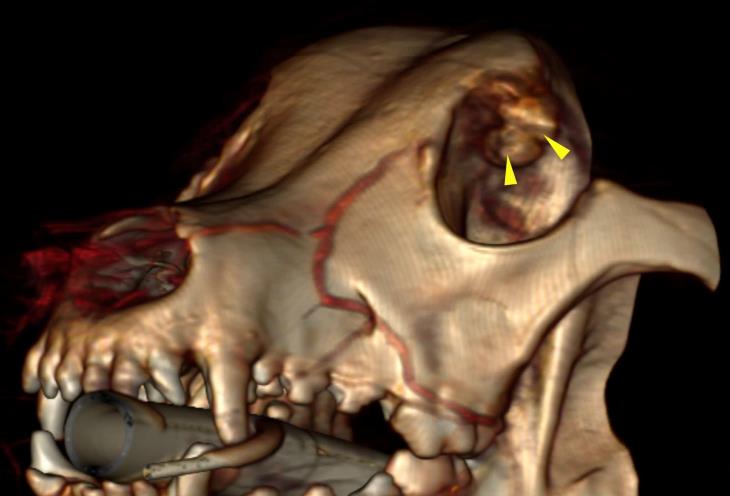

A primary neoplastic disease (osteosarcoma) was diagnosed. The 3D reconstruction shows the base of the mass, at the level of the orbit (yellow arrowheads).

Thanks to the possibility of reformatting the images in any plane, or as three-dimensional projections, a better representation of the structural anatomic relationships can be achieved.